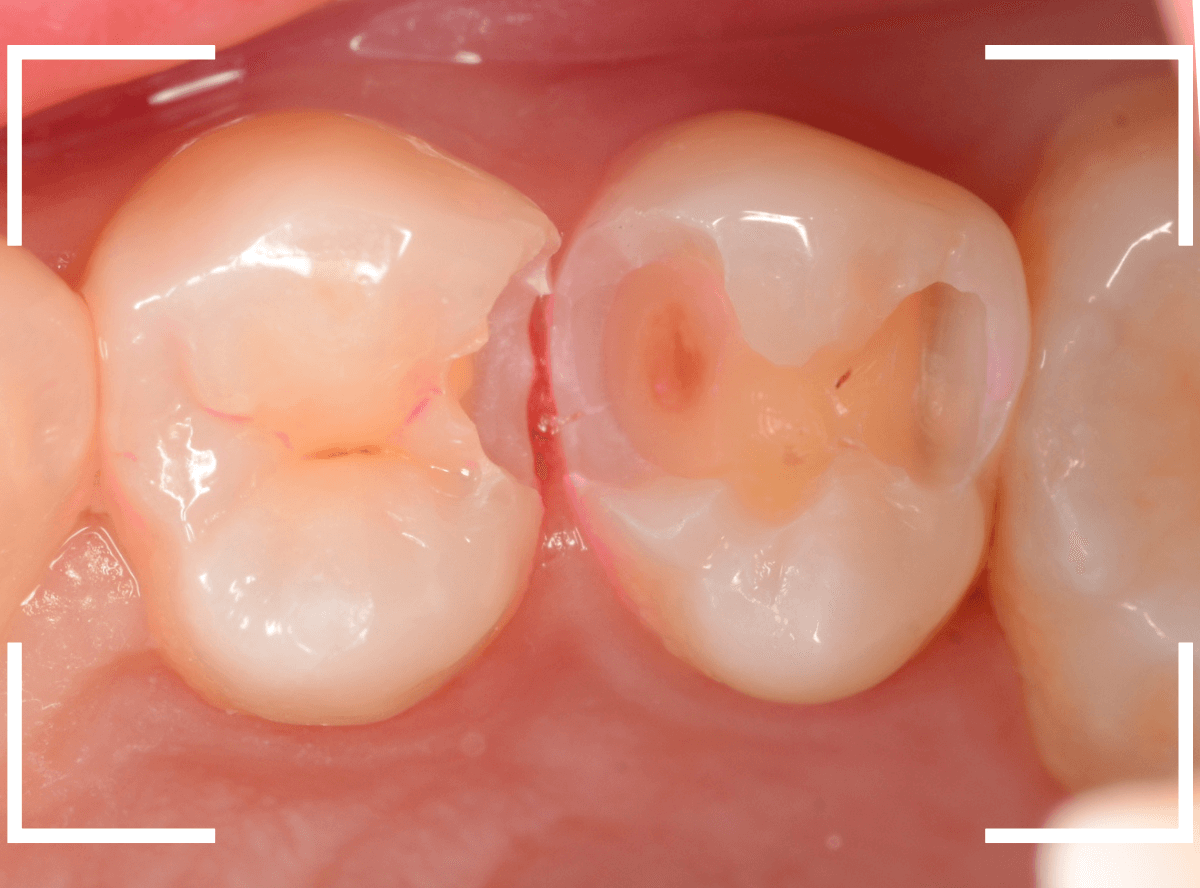

Case.23 歯のすきまから両側が大きな虫歯

「下の奥歯が痛む」という訴えで来院された患者さんのケースです。

目視でも、手前の奥歯がかけていて、中で虫歯が広がってるであろうことは予想できます。

ピンセットで歯を叩いてみても、手前の奥歯が痛むようです。

レントゲン写真で確認します。

青い線が神経、赤い線が虫歯の範囲です。

奥歯の方がより深い虫歯に見えますが、再度打診で確認したところ、やはり手前の奥歯が痛むそうです。